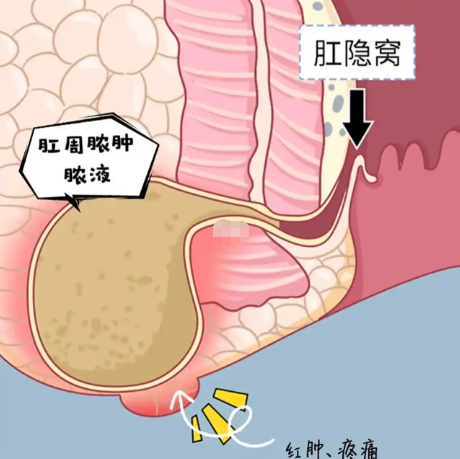

肛周脓肿是发生在肛门直肠周围的急性化脓性感染,本质上是肛腺感染后炎症向周围组织扩散所致。常见症状包括肛周持续性胀痛或跳痛、局部红肿硬块、伴随发热等全身症状,若处理不及时可能发展为复杂性的肛周坏死性筋膜炎,甚至引发全身性感染。该疾病好发于20-40岁的中青年男性,与熬夜、饮酒、辛辣饮食、久坐等生活习惯密切相关。

治疗肛周脓肿的关键在于及时进行外科引流,单纯依赖抗生素或保守治疗往往效果不佳。手术需要在充分麻醉下切开脓腔,彻底清除坏死组织并建立通畅引流。术后规范换药与创面护理至关重要,通常需要3-4周的恢复期。预防肛周脓肿应注意保持肛周卫生,避免久坐,规律作息,节制辛辣刺激食物和酒精摄入,同时积极治疗腹泻、便秘等肠道疾病,从源头上减少肛腺感染的机会。